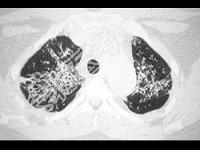

- 单项选择题女,35岁, 养鸽,咳嗽、咳痰, 结合CT图像,最可能的诊断是 ( )

A、肺隐球菌病

B、肺转移瘤

C、支气管肺炎

D、肺结核

E、肺泡癌